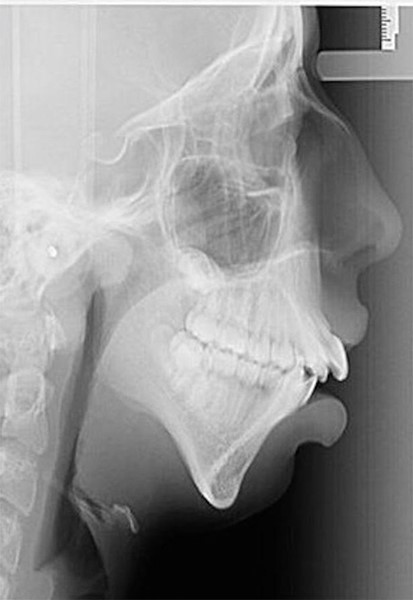

Това момиче се ражда с тежко изкривяване на челюстта, което размества цялата й захапка и положение на зъбите. Тя не могла да се храни с твърди храни и консумирала основно супи и рядко си позволявала меки „изкушения“. За месо; коричка хляб или нещо по-твърдо дори не могла да си помечтае, разказва lifebg.net.

Покрай всичките си здравословни проблеми, тя трябвало да търпи й подигравките на своите съученици, които я наричали „крокозъбел“; „изрод“ и други нелицеприятни епитети.

Подлага се на ортодонтско лечение, което продължава до завършването й. Резултатът е феноменален! Днес тя може да се похвали с 24-каратова усмивка и дори успява да сбъдне мечтата си – да бъде фотомодел!